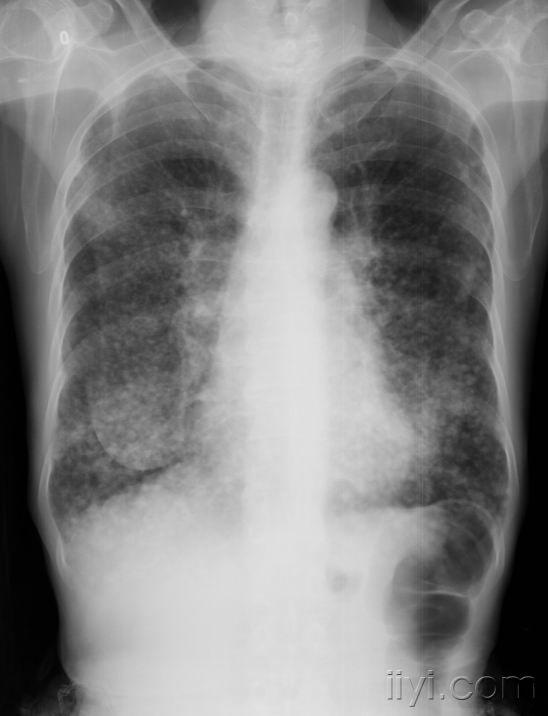

x3968:原发性肺动脉高压一例!